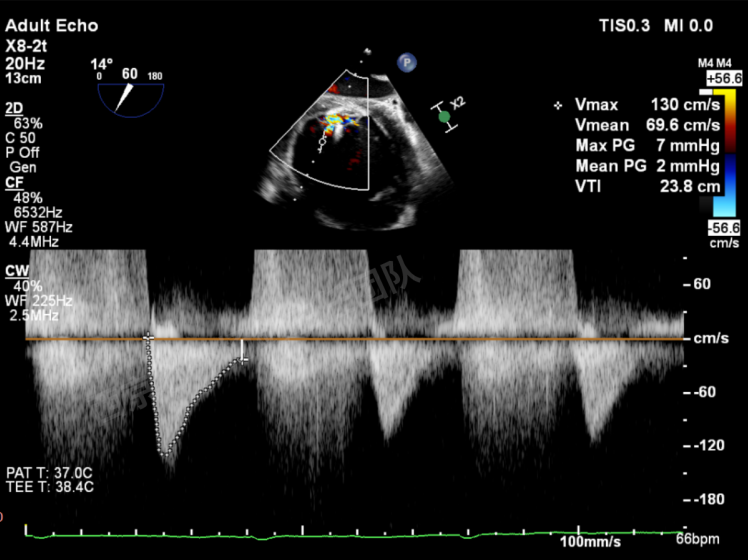

TAVR术后,全心增大,二尖瓣反流重度,三尖瓣反流重度。中量心包积液。左室严重增大,标准图像调整困难。主动脉瓣位带支架人工瓣膜瓣叶启闭正常,主动脉瓣位人工瓣上血流速度Vmax 148cm/s,PGmax 9mmHg,Vmean 86cm/s,PGmean 2mmHg, VTI 34.7cm,瓣周反流(轻)。估测肺动脉收缩压约49mmHg;左室收缩功能明显减低。LVEF:23%,EDV:364ml,ESV:221ml。

二尖瓣平均跨瓣压差1mmHg